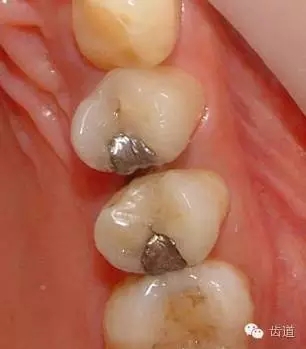

1、上頜前磨牙銀汞充填后食物嵌塞

2、去除銀汞充填物并作嵌體牙體預(yù)備

3、樹脂暫時(shí)嵌體覆蓋窩洞

4、瓷嵌體制作

5、瓷嵌體粘結(jié)